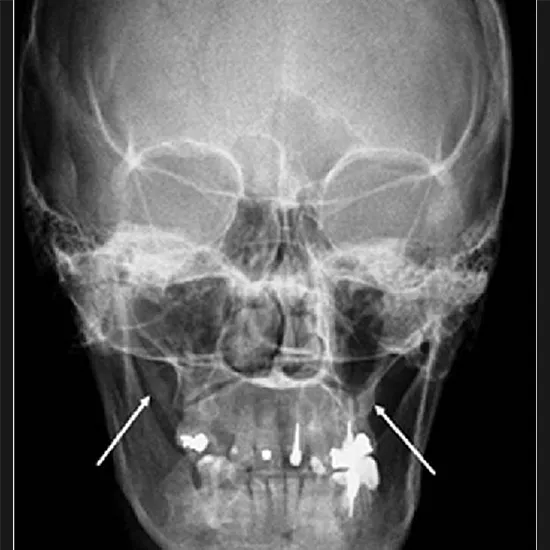

To inspect the interior of the skull, a Townes View X-Ray test is used. This test looks at the anterior exterior of the skull, which is where the rays enter the brain from front to back. A doctor may request this test to examine the inside of the skull following an incident or injury.

This view is useful in evaluating

• Petrous part of the pyramids

• Dorsum sellae

• Posterior clinoid processes

• Above three are well visualized in the foramen magnum

• Medial and lateral displacement of the skull fracture

• Neoplastic changes

• Page disease